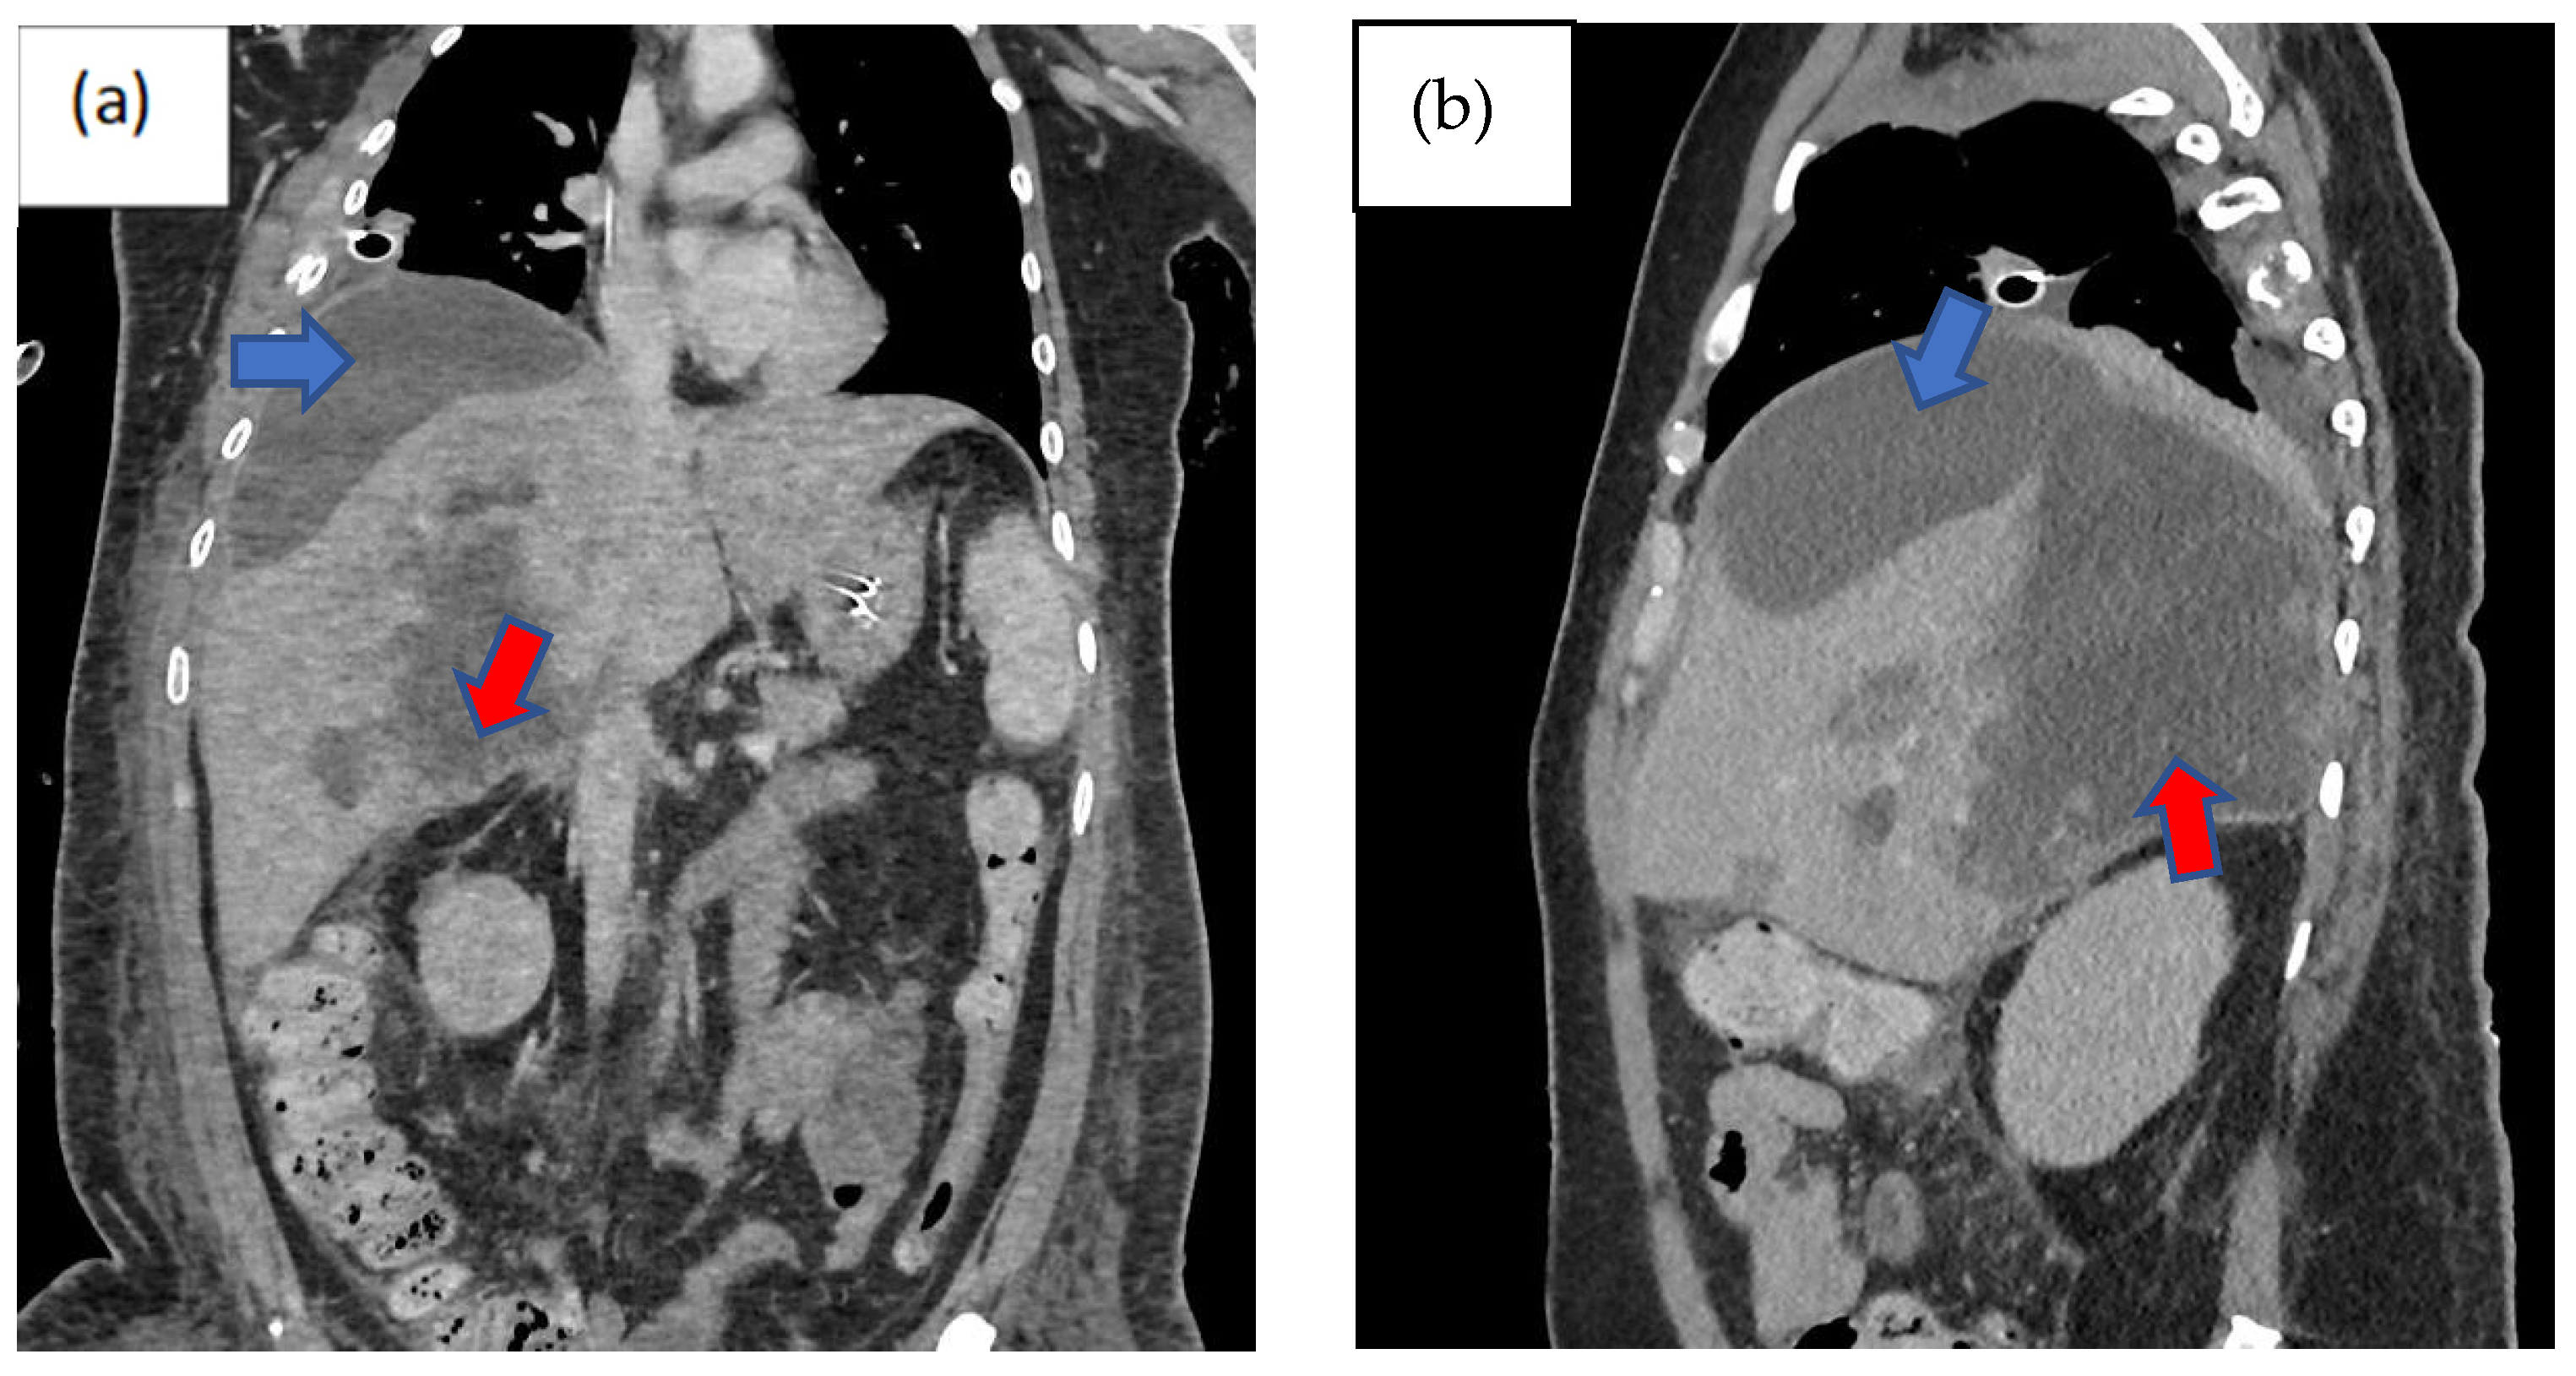

Three days following the laparotomy, the patient developed ventilator-associated pneumonia and intra-abdominal sepsis and was treated empirically with fluconazole and piperacillin–tazobactam. Repeated imaging of the abdomen was carried out in view of a poor response to antimicrobial therapy and showed the formation of biloma (Figure 1). A percutaneous subdiaphragmatic drain was inserted under computed tomography (CT) guidance by the interventional radiology team to facilitate drainage, despite being able to drain only a minimal amount, and the drain was dislodged after three days. In view of ineffective percutaneous drainage with worsening intrabdominal sepsis despite one week of adequate antimicrobial therapy, upon discussion with the hepatobiliary team, we decided to proceed with a hemi-hepatectomy for the removal of the biloma.

Imaging remains the gold standard for diagnosing bilomas, with ultrasound (US) often being the initial imaging modality used. Bilomas typically appear as well-defined hypoechoic fluid collections within the abdomen that vary in size and shape, ranging from small localized areas to larger, more extensive masses. It also has the capability of detecting the content within the biloma by showing a variety of findings ranging from well-defined collections in the liver parenchyma to extensive fluid collections across the abdomen [8]. Notably, US findings show heavily loculated bilomas are often linked to infection [9]. CT imaging can help identify the overall structure of the biloma, delineating clear margins that can be either encapsulated or non-encapsulated [10]. While CT imaging offers a more intricate view of bilomas, it lacks the capability to conclusively distinguish among various potential diagnoses, including seroma, abscess, lymphocele, liver cyst, hematoma, and pseudocyst [11]. Consequently, additional imaging modalities such as magnetic resonance (MR) imaging or hepatobiliary cholescintigraphy may be necessary to help validate the diagnosis. Direct sampling of the biloma together with these imaging techniques will also help with the diagnosis [10]. In T1-weighted images, bilomas will display low signal intensity, whereas in T2-weighted images, high signal intensity is seen [12]. Furthermore, MR imaging can help to define the characteristics of a biloma. While contrast infrequently penetrates the biloma, rim enhancement and septations occasionally occur due to reactive inflammation and infection [12]. Hepatobiliary cholescintigraphy serves as a highly efficient non-invasive imaging technique for diagnosing and strategizing treatment for bilomas by utilizing a radiotracer known as Tc-99m iminodiacetic acid, which is commonly referred to as hepatobiliary iminodiacetic acid (HIDA) imaging [10,13]. HIDA imaging exhibits a high level of sensitivity in detecting bile leaks [13]. Nonetheless, it lacks the ability to offer detailed imaging of the surrounding anatomical structures. Single positron emission computed tomography (SPECT) is another imaging technique that has the ability to furnish more intricate imaging of potential leak locations, proving particularly valuable in planning percutaneous image-guided drains [10]. Endoscopic retrograde cholangiopancreatography (ERCP) and percutaneous transhepatic cholangiogram (PTC) can be considered not only for diagnostic tests but also may offer some degree of intervention either percutaneously or endoscopically [13]. Other minimally invasive investigations available are CT-guided sampling technique and US-guided sampling technique. However, these techniques require laboratory assistance to analyse the sample collected [10]. In our case, CT imaging was sufficient to give us the information we need. The initial CT imaging (Figure 1) revealed a rim-enhancing lesion surrounding the biloma, suggesting a potential infective biloma. However, we did not perform a biopsy and or staining hepatic tissue during the hemi-hepatectomy to definitely confirm that Rhodotorula mucilaginosa originated from the biloma itself. This limitation underscores a key aspect of our study, highlighting the need for further investigations to establish a direct link between the presence of Rhodotorula mucilaginosa and the biloma. MR imaging was not performed in this patient which shows another limitation in this case. MR imaging might indicate presence of septations within the biloma and this might be the reason why percutaneous drainage failed in this patient.

Figure 1. Computed tomography scan of the abdomen non-contrasted phase showing heterogenous areas consisting of hematoma and laceration at segments V, VI, VII, and VIII extending down to the subhepatic region (red arrow). Inferiorly, it extends down to the hepatic flexure, just lateral to the right pararenal space. Another subcapsular collection was seen adjacent to right liver lobe (blue arrow): (a) coronal view, (b) sagittal view, and (c) axial view, with findings as aforementioned.